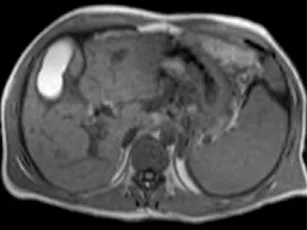

Figure 4. Acquisition 2D de multiples coupes épaisses, selon une distribution radiaire en restant centré sur le bas cholédoque (A).

L’acquisition (B) montre une dilatation de la VBP avec un arrêt cupuliforme au niveau du bas cholédoque (tête de flèche).

On suspecte une lithiase, mais sans pouvoir éliminer une image de pseudo- calcul liée à une contraction du sphincter.

L’acquisition radiaire suivante (C), lors d’une ouverture sphinctérienne, établit formellement le diagnostic, en montrant le passage de bile autour d’un calcul enclavé du bas cholédoque (tête de flèche).